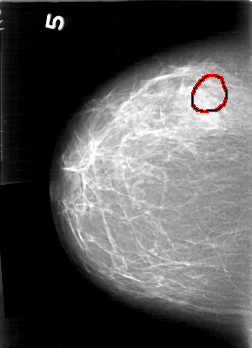

D_4167_1.LEFT_MLO

FILE: D_4167_1.RIGHT_CC.OVERLAY

TOTAL_ABNORMALITIES 1

ABNORMALITY 1

LESION_TYPE CALCIFICATION TYPE PUNCTATE-AMORPHOUS DISTRIBUTION CLUSTERED

ASSESSMENT 0

SUBTLETY 2

PATHOLOGY BENIGN

TOTAL_OUTLINES 1

BOUNDARY